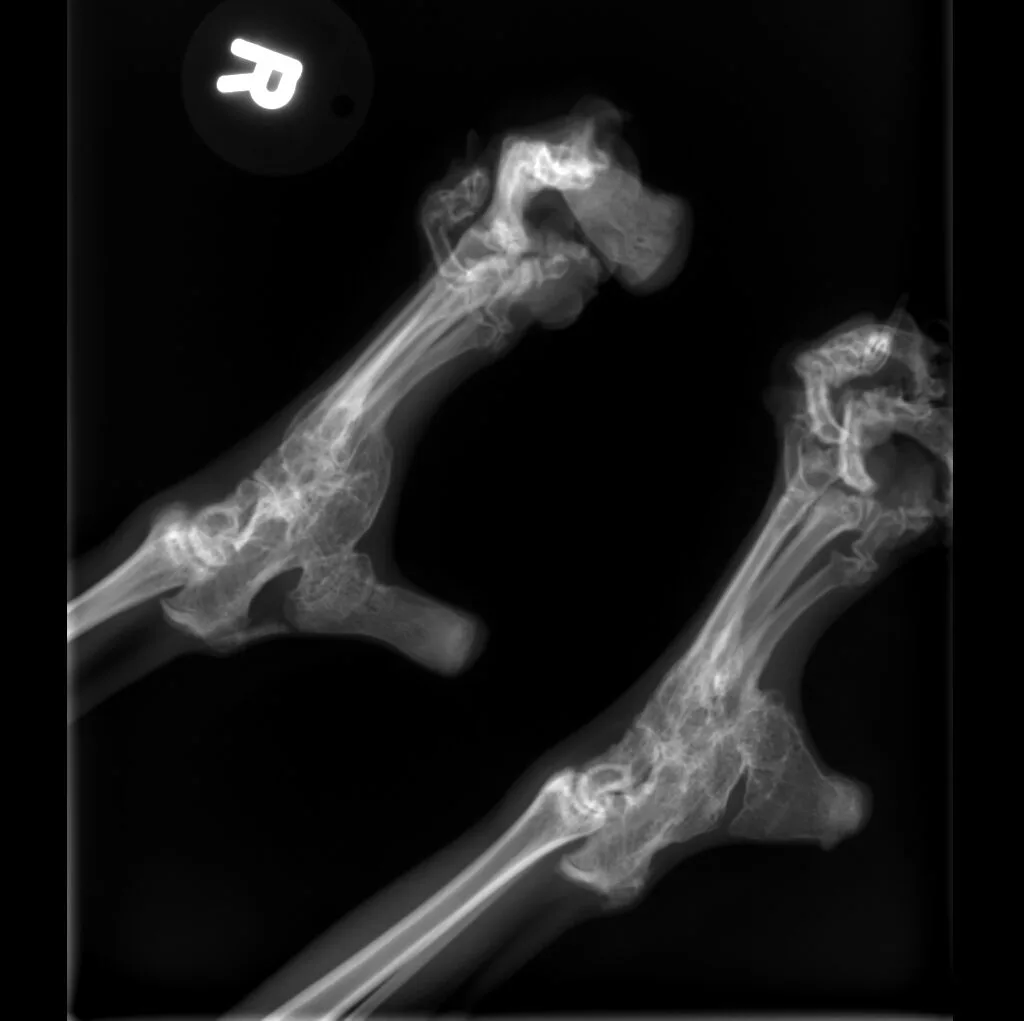

🔹 Lameness & Joint Issues – Identifying fractures, arthritis, and mobility concerns

Digital radiography offers superior imaging quality and precision compared to traditional X-ray techniques. It allows us to detect hidden health issues early, leading to faster and more effective treatments.